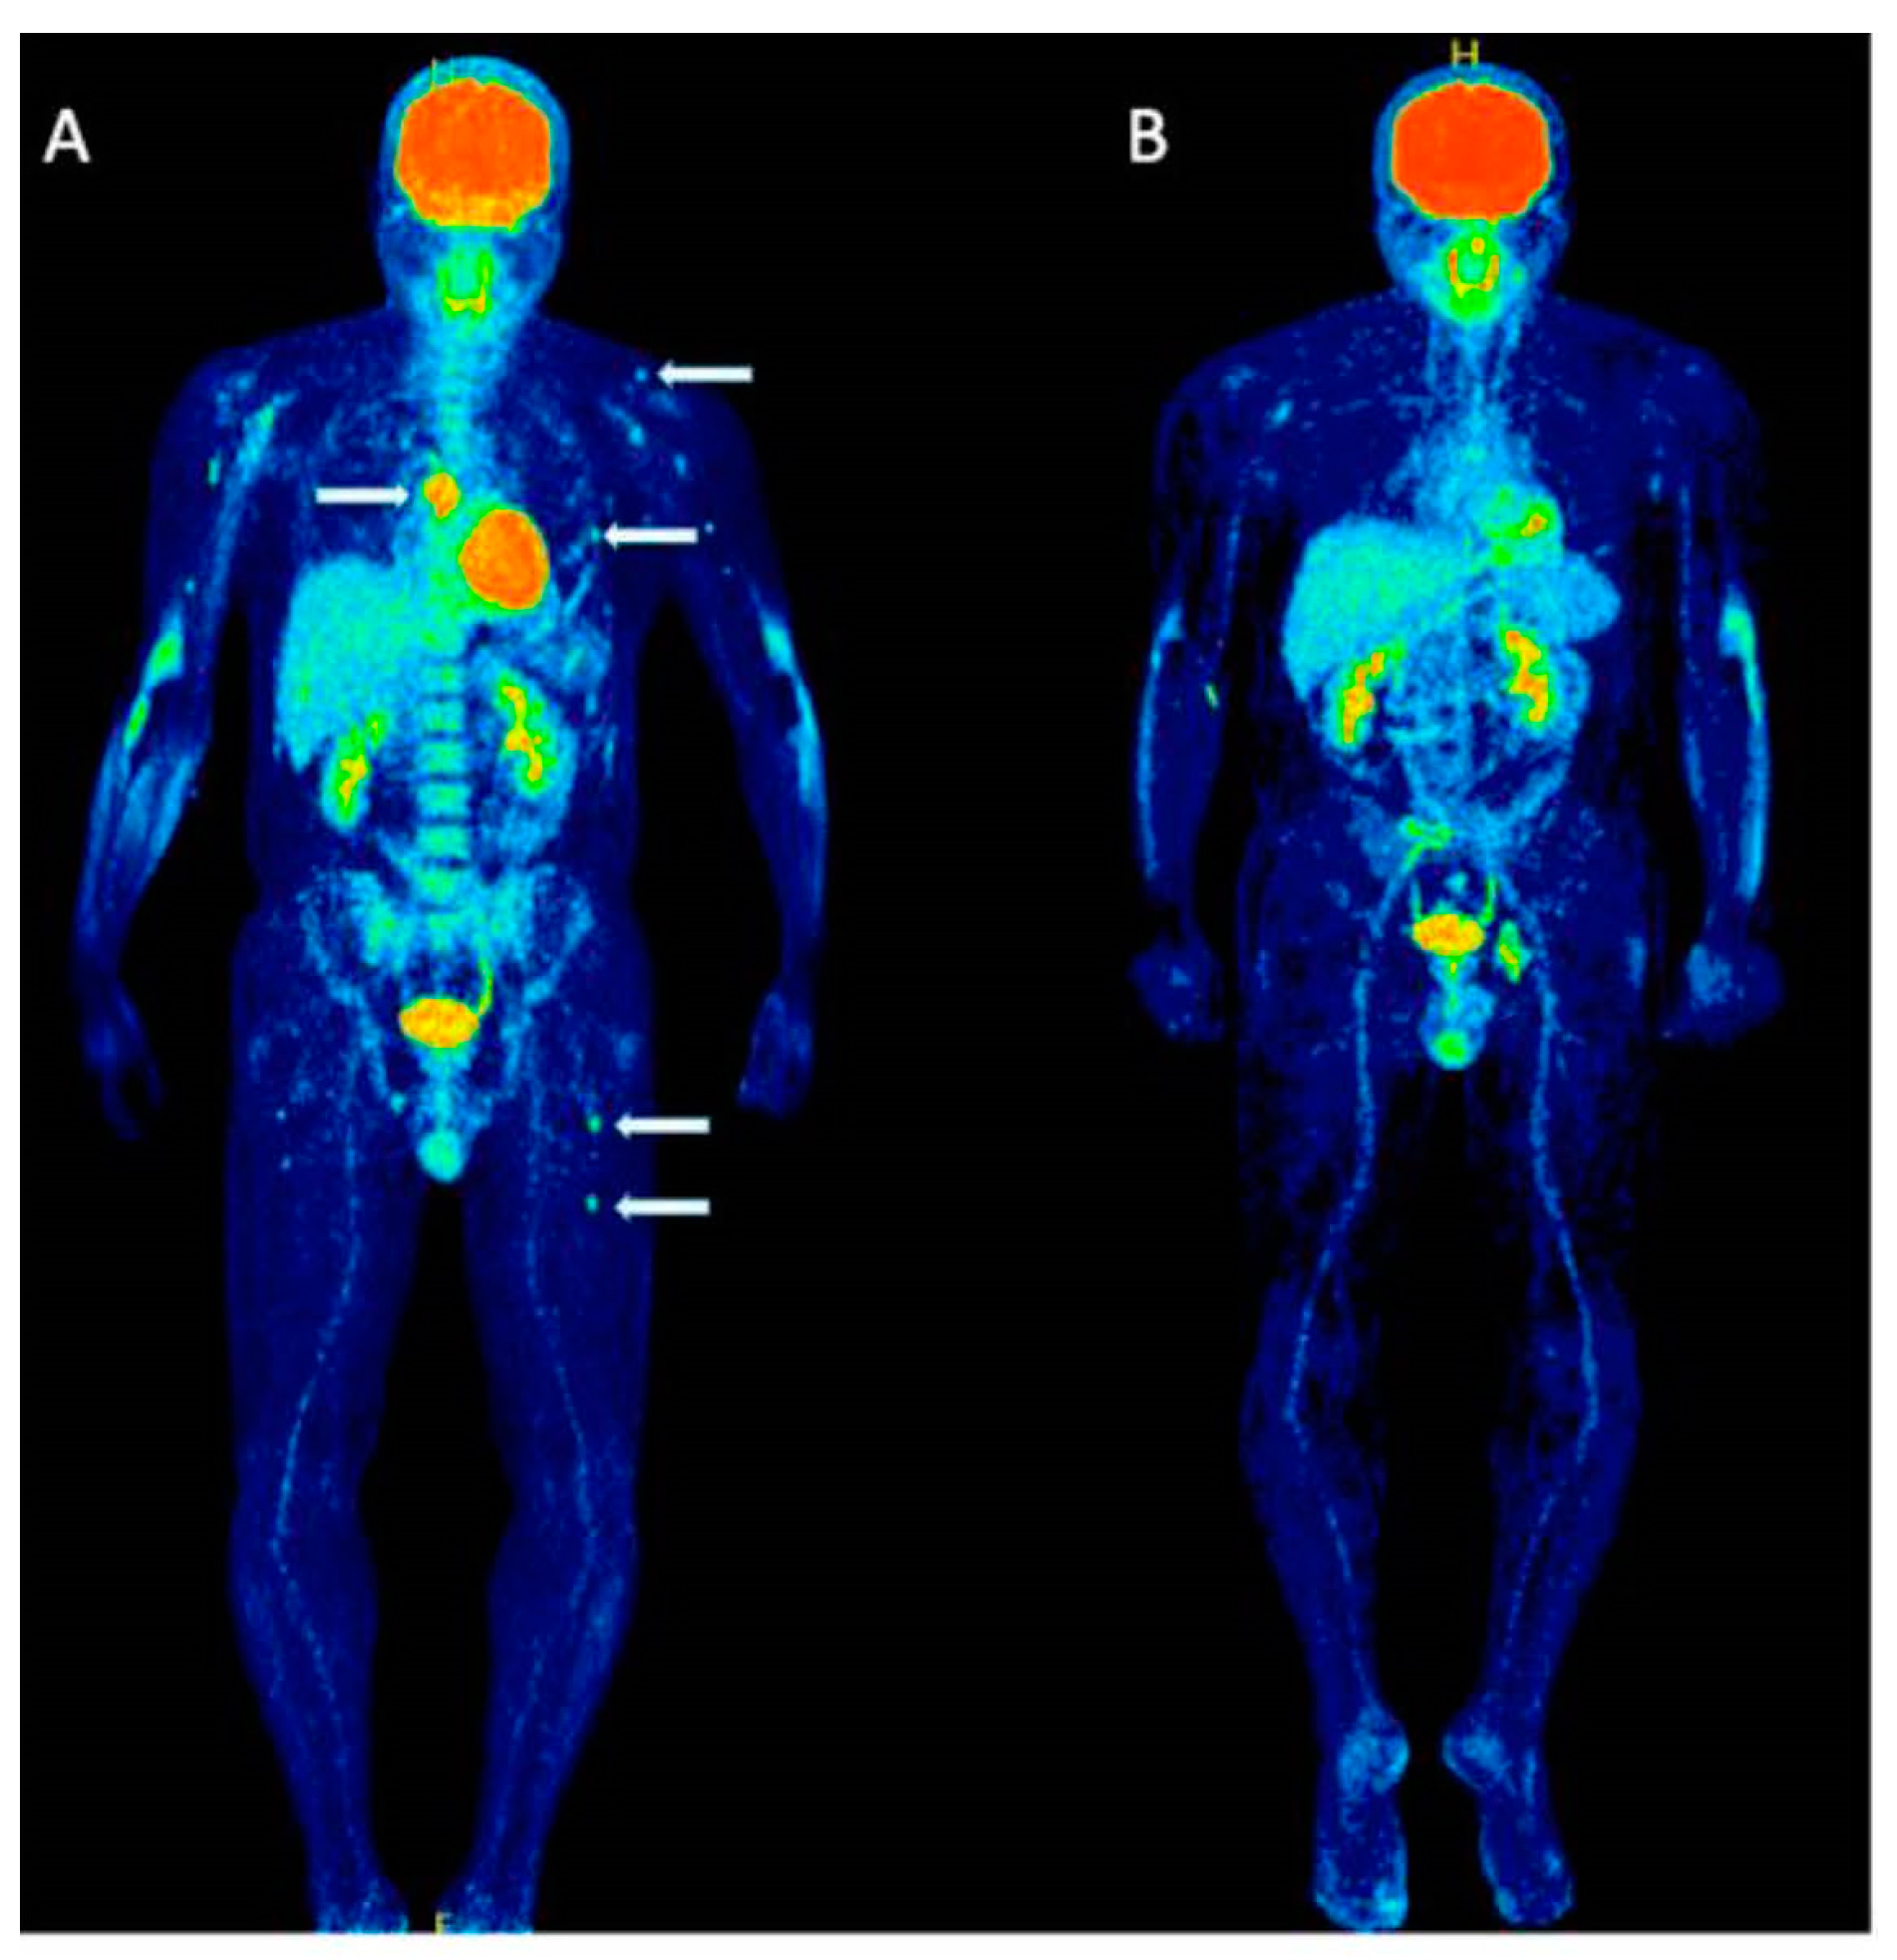

Evaluating the response to treatment is a significant area where [18F]FDG PET/CT might offer greater utility compared to conventional imaging methods [23] (Figure 4 and Figure 5). By analyzing the metabolic behavior in areas with clonal plasma cell growth, [18F]FDG PET/CT can precisely gauge and quantitatively measure alterations in cancer cell activity following therapeutic interventions [24,25,26,27,28,29]. Furthermore, there is a robust correlation between negative [18F]FDG PET/CT results and a highly positive response to treatment in myeloma patients [20].

Figure 4.

This figure presents the case of a 39-year-old patient with symptomatic multiple myeloma (MM) who was being prepared for high-dose therapy (HDT) and autologous stem cell transplantation (ASCT). This patient underwent an [18F]FDG PET/CT scan both before and after treatment. The maximum intensity projection (MIP) of the [18F]FDG PET/CT scan before treatment (A) revealed a combination of intense, widespread uptake in the axial skeleton and multiple focal bone marrow lesions in locations such as the sternum, ribs, humerus, scapula, and femur (indicated by arrows). The follow-up [18F]FDG PET/CT MIP after HDT and ASCT (B) demonstrated a complete remission of both the diffuse bone marrow uptake and the focal MM lesions. Figure 2, PMID: 31905752, PMCID: PMC6982887, OPEN ACCESS.